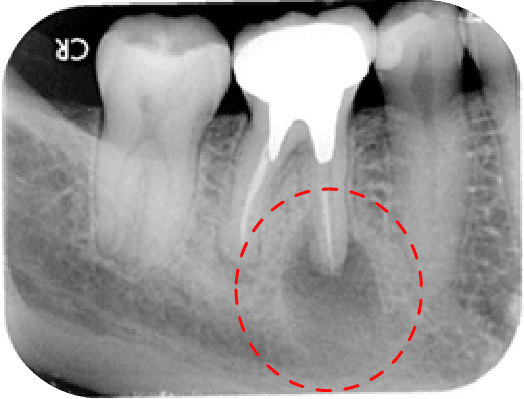

左圖中第一大臼齒兩個牙根皆因為根管內的感染造成根尖周圍炎(紅線中黑黑的地方),在根管治療後追蹤一年可發現骨頭都已經恢復正常的樣子